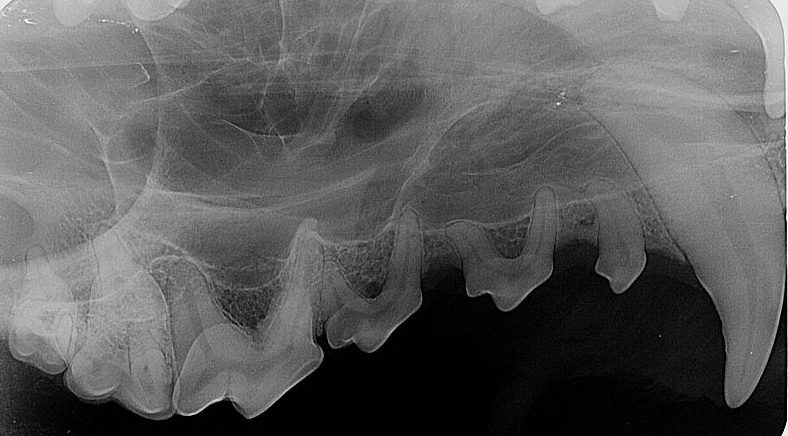

Wir bieten zu jeder professionellen Zahnreinigung und Zahnbehandlung das Dentalröntgen an. Unser Speicherfolienscanner Visiovet CR7 wurde speziell für die intraorale Röntgendiagnostik in der Veterinärmedizin entwickelt. Die digitale Bildgebung ermöglicht optimale Bildergebnisse für eine sichere Befundung und Folge dessen richtige Behandlung von Zahnerkrankungen bei Ihnen Vierbeinern. Der fein fokussierte Laserstrahl spielt eine entscheidende Rolle, wenn es um die höchste Auflösung geht. Feinste Läsionen, Parodontalerkrankungen oder Frakturen werden sichtbar, die Ergebnisse sind brillant und blitzschnell.